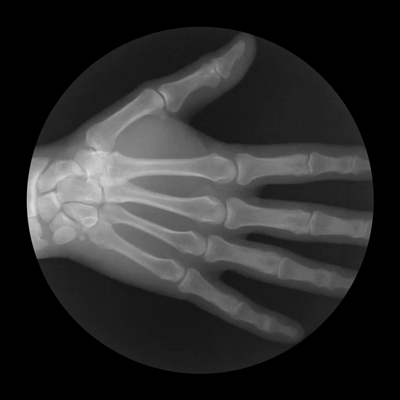

8. Muscle of the Hand